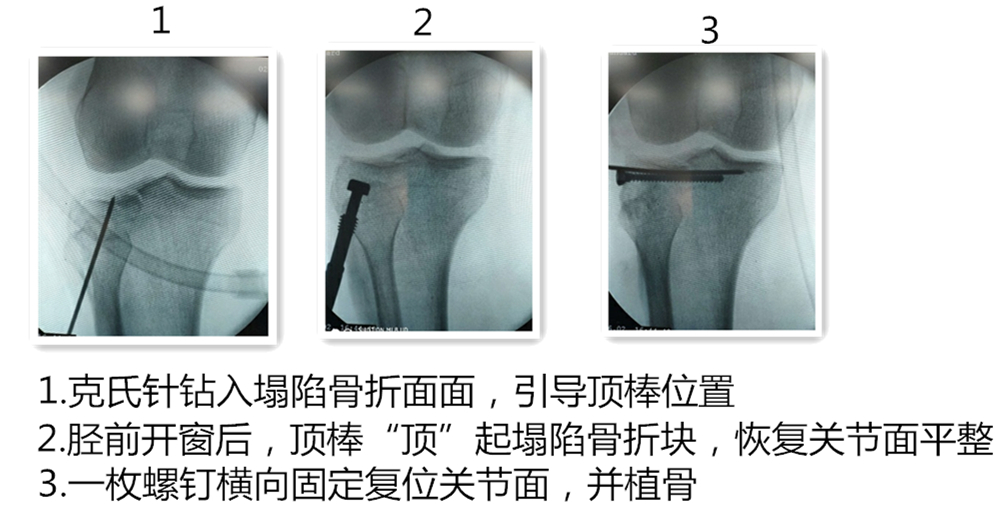

手术压缩骨块复位示意图

术中的所拍摄的图片